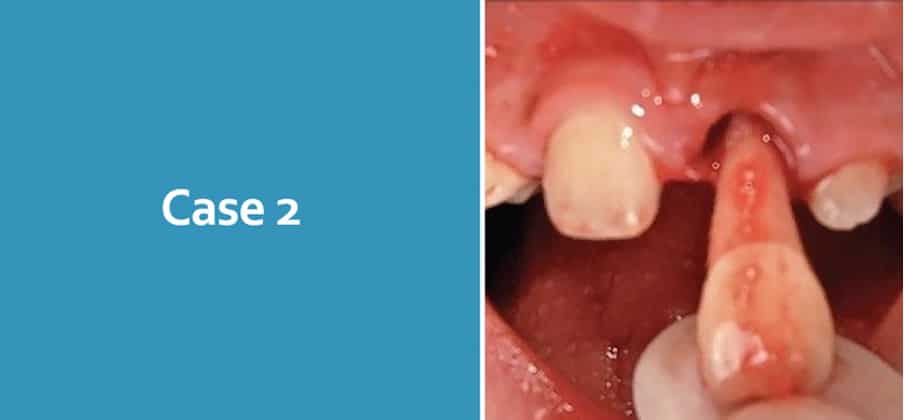

Case 2

8-year-old attends following an avulsion UL1 at school. He attends with his school teacher who has brought the tooth in milk. She reports that the tooth has been in milk for 45 minutes. The tooth has an open apex.

What are you concerns?

Concerns – Case 2

Consent

Safeguarding / NAI

Act in patient best interest

Condition of tooth

Medical background

Total extra-oral time (inc. dry time)

What is your immediate management?

Contact parents

Medical history and history of trauma

Clean the root surface with saline

LA

Examine the alveolar socket. If there is a fracture of the socket wall, reposition it with a suitable instrument

Irrigate the socket with sterile saline to remove coagulum and debris

Replant the tooth slowly with slight digital pressure

Verify normal position of the replanted tooth clinically and radiographically

Apply a flexible splint for up to 2 weeks

Suture gingival lacerations, especially in the cervical area

Administer systemic antibiotics

Amoxicillin/penicillin (first line)

Tetracycline – Doxycycline BD 7 days (<12 year – Consider risk of discolouration)

Tetanus

What is your long-term management?